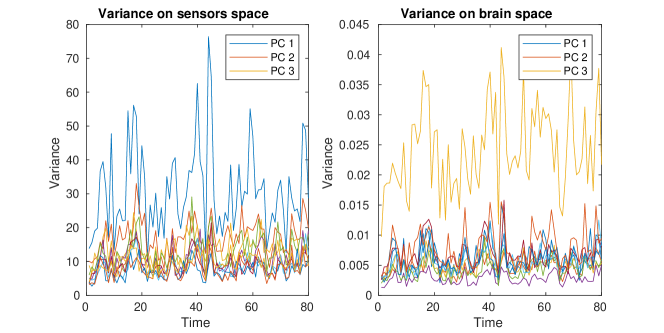

A regularization parameter common to all the PC components is chosen by inspecting the plot of the regularity of the first PC covariance functions () versus the residual norm, for different choices of the parameter. This is a version of the L-curve plot (Hansen, 2000) and is shown on the left panel of Figure B.2. Here we show the results for , in the appendices we show the results for . The energy maps of the estimated , and resulting from the analysis are shown in Figure 11. These are associated with the first three PC covariance functions , and . High intensity areas, in yellow, indicate which areas present high average interconnectivity, either by means of positive or negative correlation in time.

In Figure 12, we show the plot of variances associated with each time segment, describing the variation in time of the PC covariance functions, hence the variation in interconnectivity. The variance can be either defined on the sensors space, by normalizing the PC covariance functions , with the forward operator, or on the brain space, by normalizing the PC covariance functions on the brain space . Due to the presence of invisible dipoles, which are dipoles that display zero magnetic field on the sensors space, the two norms can be quite different, leading to different average variances for each PC covariance function. Due to the high sensitivity of the source space variances on the choice of the regularization parameter, we focus on the estimated variances on the sensors space.

We have also applied our model to the covariances obtained by subdividing the MEG session in segments. As expected the PC covariance functions, shown in Figure B.5 are very similar. However, the variances, in Figure B.4, show higher variability in time, which can be partially explained by the fact that shorter time segments lead to covariance estimates that have higher variability.

In Figure B.3-B.4 we show respectively the plots of the estimated PC covariance functions and associated variances from the dynamic functional connectivity study on segments with regularization parameter .

In Figure B.5-B.6 we show the estimated PC covariance functions and associated variances from the dynamic functional connectivity study on time segments with regularization parameter .